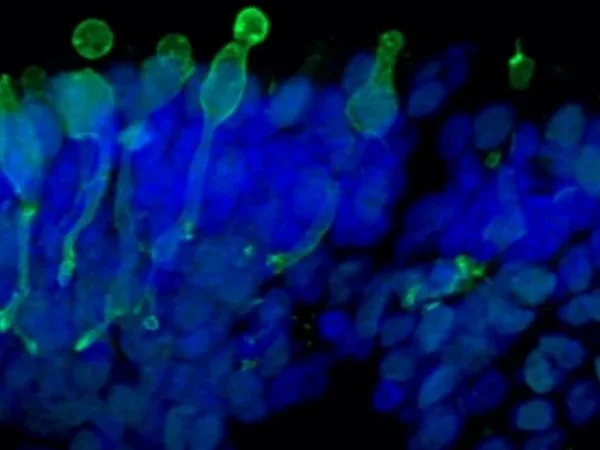

Localization and distribution of Müller glia cells (CRALBP, red) in retinal organoids. Nuclear DAPI staining (blue). Image Credit: Newcells Biotech